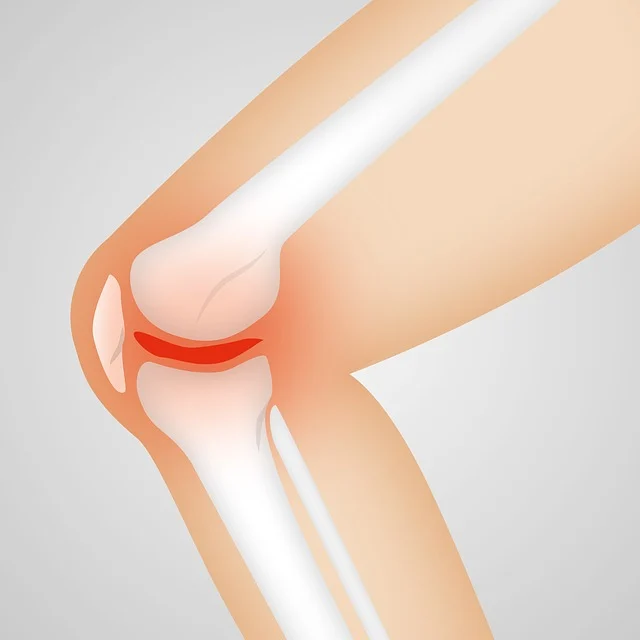

인공관절은 무릎에 통증과 뼈와 뼈가 맞닿아 무릎통증과 마모절감 수술에 제공되는 의료기기입

니다. 무릎통증이 너무 심해 걷지 못하게 되어 인공관절 수술을 하게 되는 것입니다. 매우 심각한 무

릎통증과 걷지도 못하게 되는 퇴행성 관절염 4기가 되기 전 진단을 받고 치료하는데 관심을 가져야

한다.

- 인공관절은 연골이 마모가 되어 뼈와 뼈가 부딪치면서 고통을 겪으며 걷지를 못하게 되는 퇴행

성 관절염 수술에 공급되는 의료수술 기기입니다.

퇴행성관절염 증상.

- 통증은 퇴행성관절염의 대표적인 증상입니다.

- 무릎에 물이 차는 증상, 붓기도 합니다.

- 퇴행성 관절염의 심화.

- 다리 모양의 변형 및 통증.

- 보행장애.

- 관절의 구축.

퇴행성관절염 4기는 연골이 거의 다 마모가 된 뼈와 뼈가 맞닿은 상태입니다.